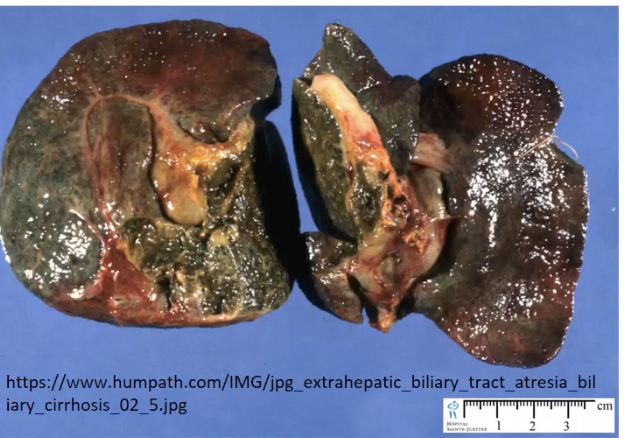

Biliary Atresia

a congenital condition with absence or underdevelopment of the bile ducts —> bile accumulation, liver damage, and jaundice in infants.

Type III Biliary Atresia =

Complete absence of a biliary tree

Green Liver = Biliary Atresia

Biliary Atresia